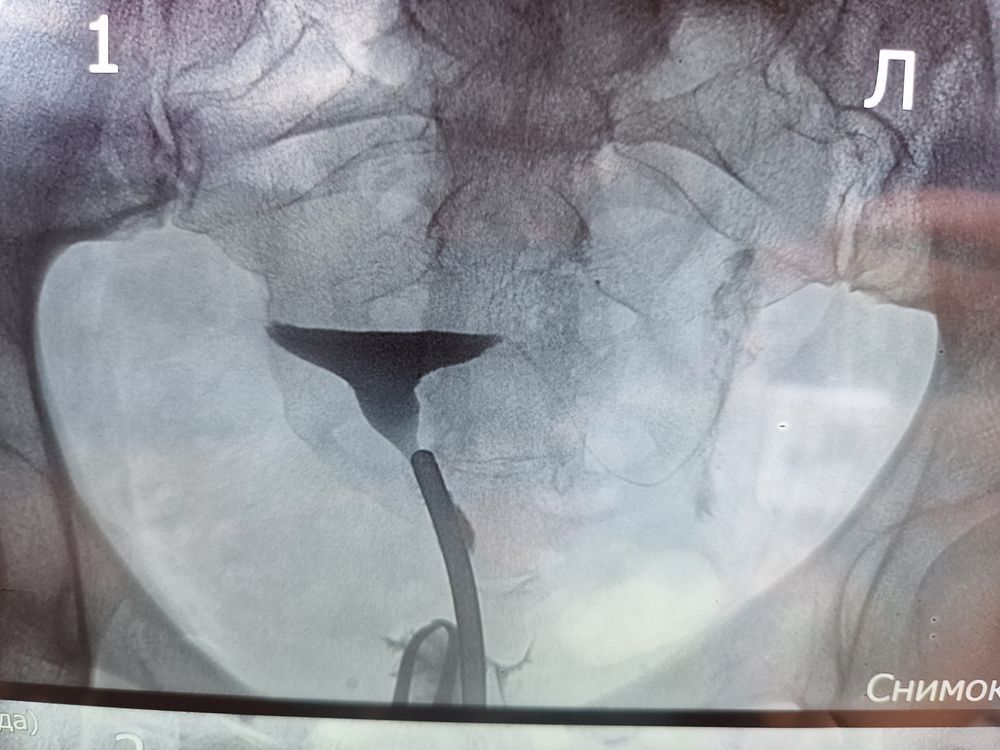

Начали вводить контраст... Изначально боли не было, был лёгкий холодок от контраста, потом ввели ещё больше, и тут начало тянуть низ живота, как при сильном ПМС, остановились, подождали, боль ушла. Ввели нужное количество, сделали снимки.

По снимкам оказался гидросальпинкс, в ампулярном отделе, и с этим результатом пошла к РЕ (04.07.23)